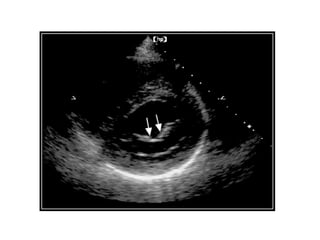

M mode

• As the aortic jet cascades across the anterior mitral leaflet, it

creates a high frequency fluttering.

• Rapid sampling rate of M mode echo needed for detection.

• One of the earliest examples of use of M mode echocardiography

to indirectly assess valve disease.

• In Acute AR, premature closure of the mitral valve due to

rapidly increasing LV diastolic pressure.

• Hyperdynamic IVS motion due to excessive volume overload

on LV due to chronic AR. – exaggeration of normal diastolic